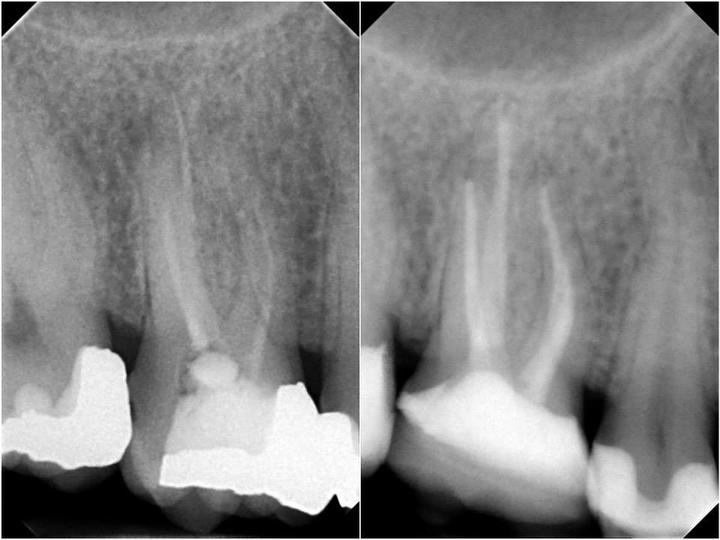

Príbeh: náš pacient Peter (34 rokov) k nám prišiel s tým, že nebol spokojný so starými, nevyhovujúcimi amalgánovými plombami. Najskôr sme staré amalgánové výplne odstránili. Pri práci používame tzv. kofferdam (modrá blana), aby sme zabezpečili úplnú izoláciu pracovného poľa (nejdú nám na ošetrované zuby sliny a do úst nejdú prípravky používané na ošetrovanie, čo chráni aj pacienta). Po vymenení 3 výplní sme na poslednom zube prerábali koreňovú výplň a nalepili keramickú onlaye výplň. Výsledok je maximálne estetický. Staráme sa o vaše zuby ako o vlastné. Môžete sa na nás spoľahnúť.